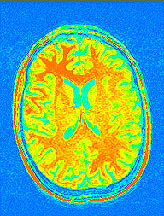

The staff will let me know when I am finished, and it is time to come out of the scanner. After I am finished, I can go into the room next to the scanner and look at some of the pictures of my brain.